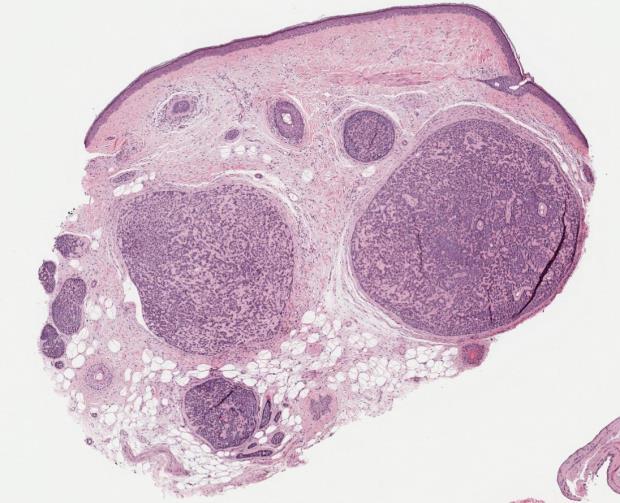

• Can occur sporadically or as part of a syndrome

• Typical morphological findings: Epithelioid and naevoid components with associated lymphoid aggregates